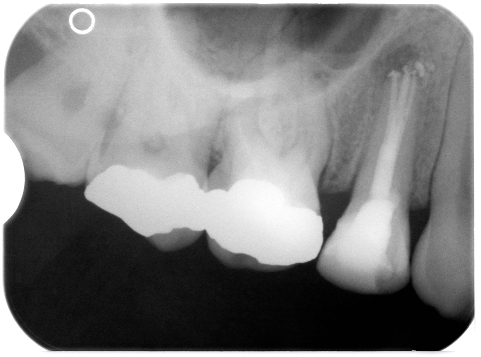

3 Veröffentlicht 16. September 2009 am 481 × 357 in 3 Beine, sicherer Stand – Apikale Aufhellung (13)